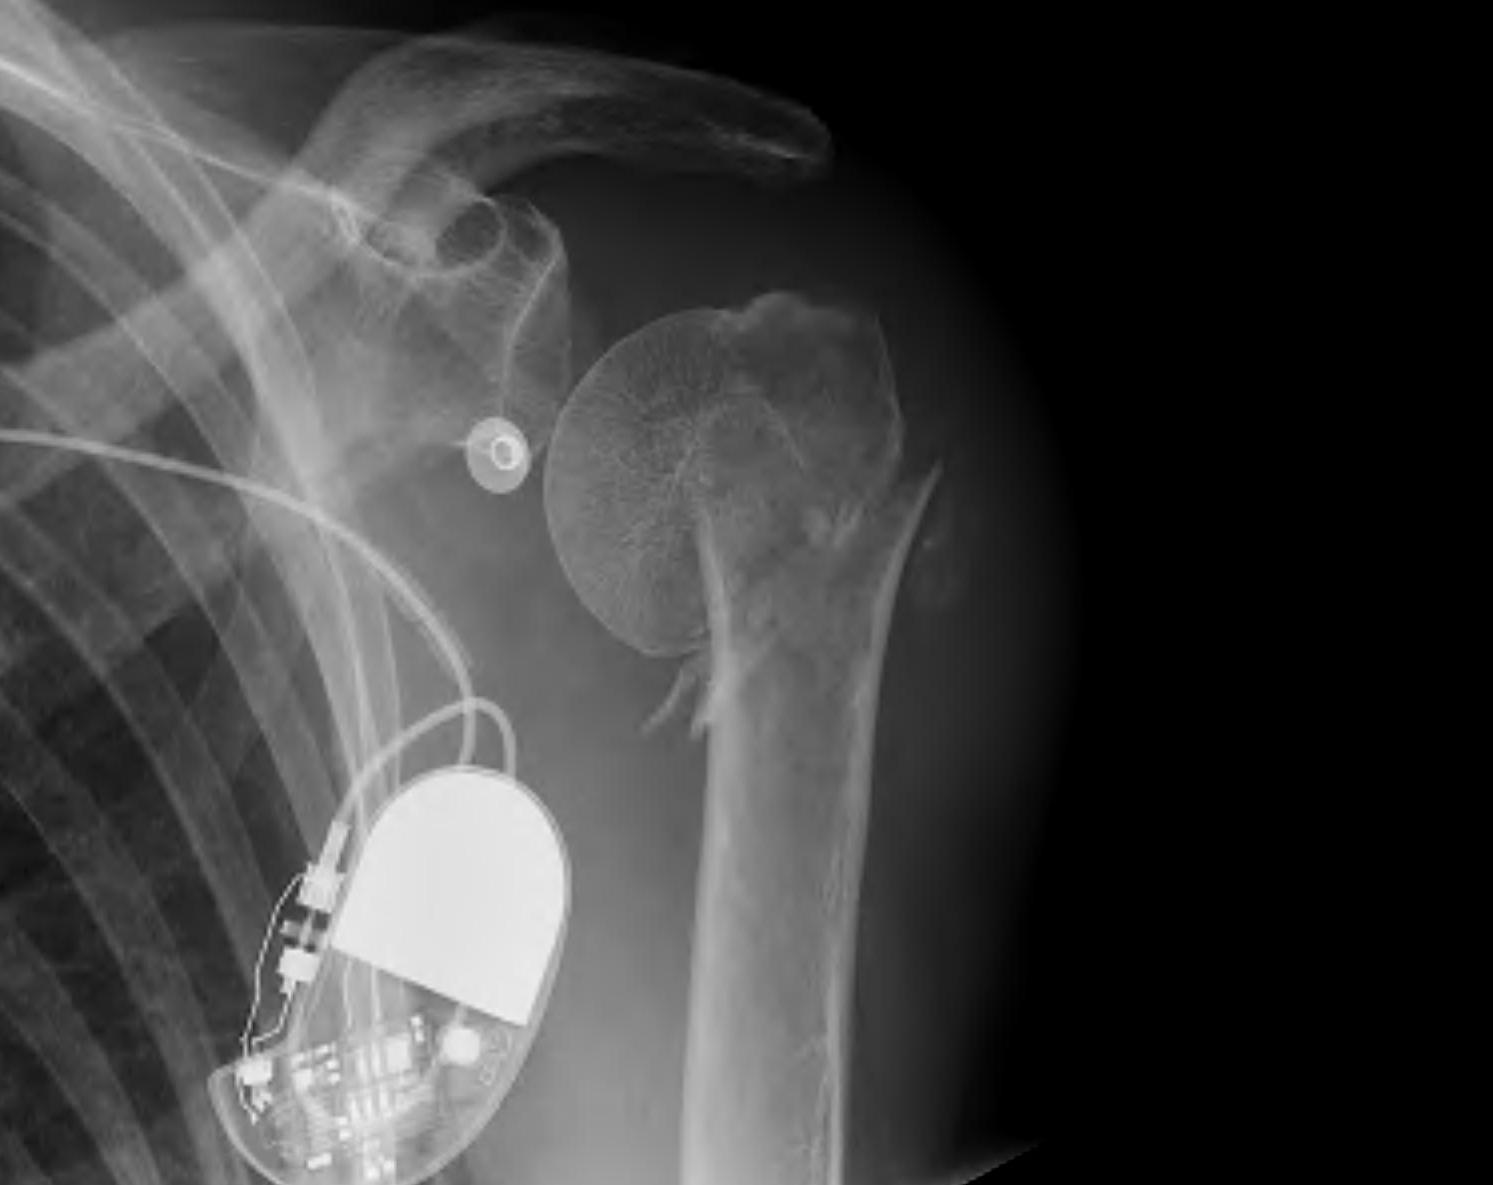

proximal humerus fracture Background ORIF with locking plate Arthroplasty Greater tuberosity fractures Lesser tuberosity fractures / avulsions Book traversal links for Proximal humerus fractures ‹ Pectoralis Major Tears Up Background ›